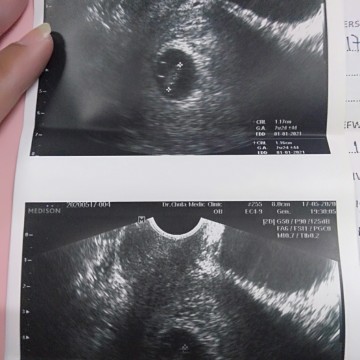

7w2d ค่ะ